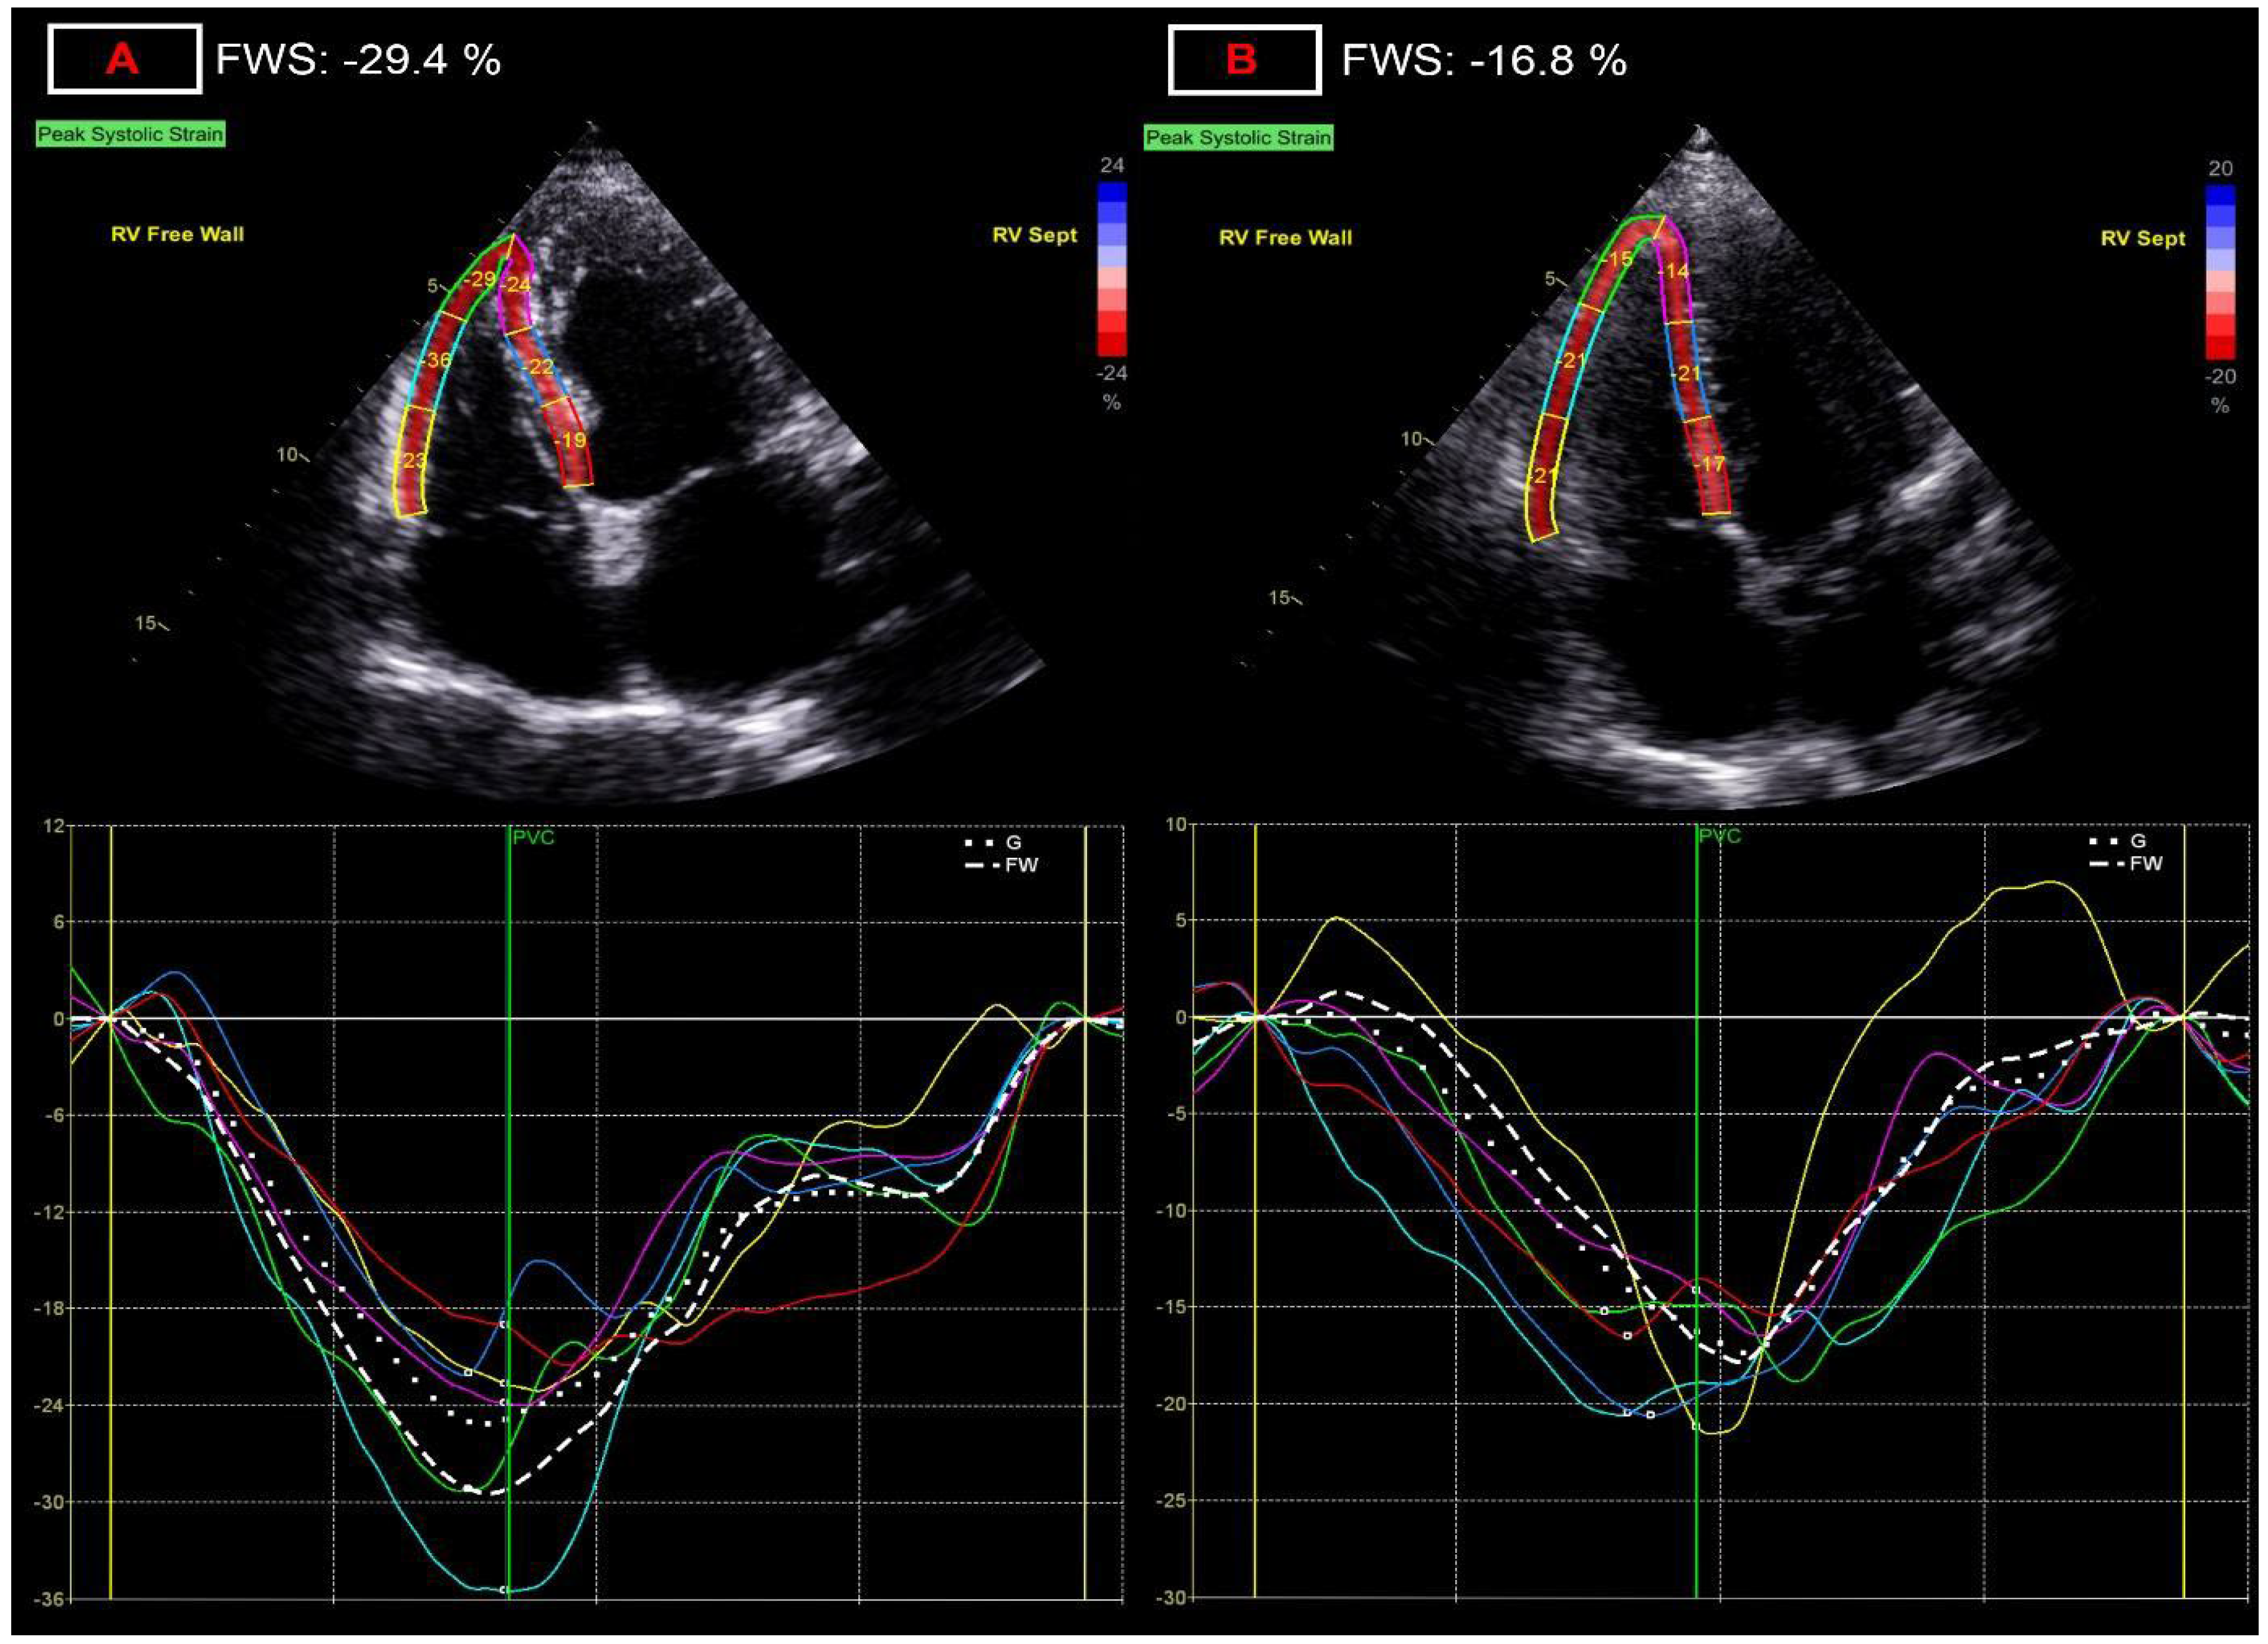

3.4. Dimensional and Functional Parameters of the Right-Side of the Heart

- Along with non-invasive measurement of stroke volume, deformation imaging appears to be able to detect the most pronounced relative difference for both left and right ventricular function, with left ventricular global myocardial work index and right ventricular free wall strain being the most robust alteration;

- These minor changes are difficult to utilize on a single patient basis, however, LV myocardial work and RV free wall strain seem to be the most sensitive and reproducible 2D echo-based functional parameters for screening for cardiac injury and follow-up;

| tricuspid annular plane systolic excursion, mm | 23.75 ± 2.8 | 22.5 ± 3.4 * | 5.3 |

| right ventricular free wall strain, % | −26.6 ± 3.80 | −23.8 ± 4.0 *** | 11.7 |